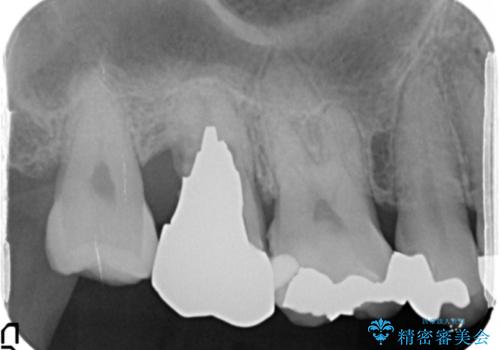

精査したところ、右上の奥歯(右上7)はう蝕が深く骨吸収も進行しており保存不可能な状態でした。

金属アレルギーの疑いがあり、インプラントも避けたいとの患者様のご希望により、親知らずを移植することにしました。

移植がうまくいかない可能性を考慮し、ブリッジもできるよう隣の親知らず(右上8)は残し、反対側の親知らず(左上8)を移植しました。